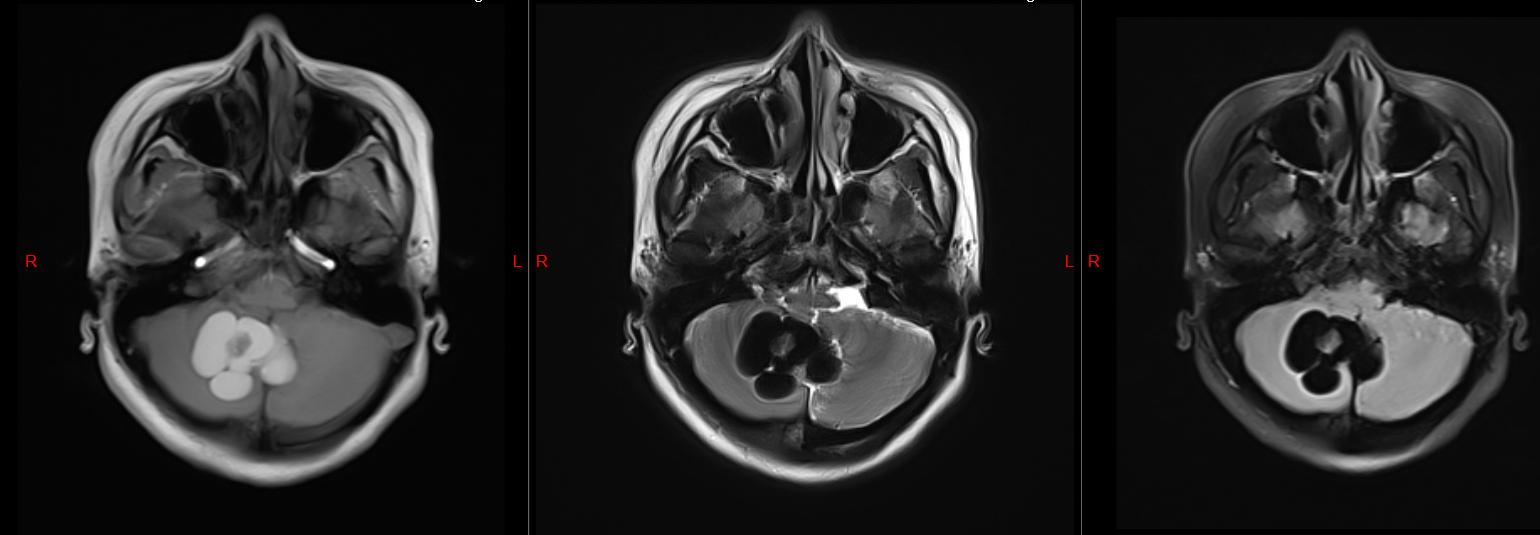

头颅磁共振检查结果显示

我的小脑上长了一个 肿瘤

压迫脑干

并且还有 脑积水

创伤外科二病区主任、主任医师张辉:结合目前症状和影像学检查显示,你的小脑肿瘤考虑皮样囊肿的可能性大,且合并梗阻性脑积水,需要进行手术治疗。

皮样囊肿是一种比较少见的颅内先天性良性肿瘤,属 先天性疾病 ,起源于异位的胚胎上皮细胞,是胚胎发育早期在神经沟封闭时将部分皮肤组织带入的结果。

术后复查头颅磁共振

肿瘤完整切除